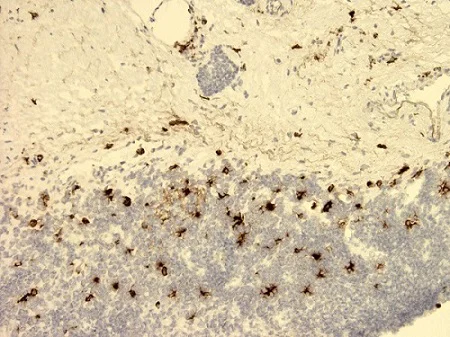

Immunohistochemistry (Frozen sections) - Anti-SLPI antibody [31] (AB17157)

Immunohistochemical analysis on human tonsil frozen sections with ab17157 at a 1 : 50 dilution.